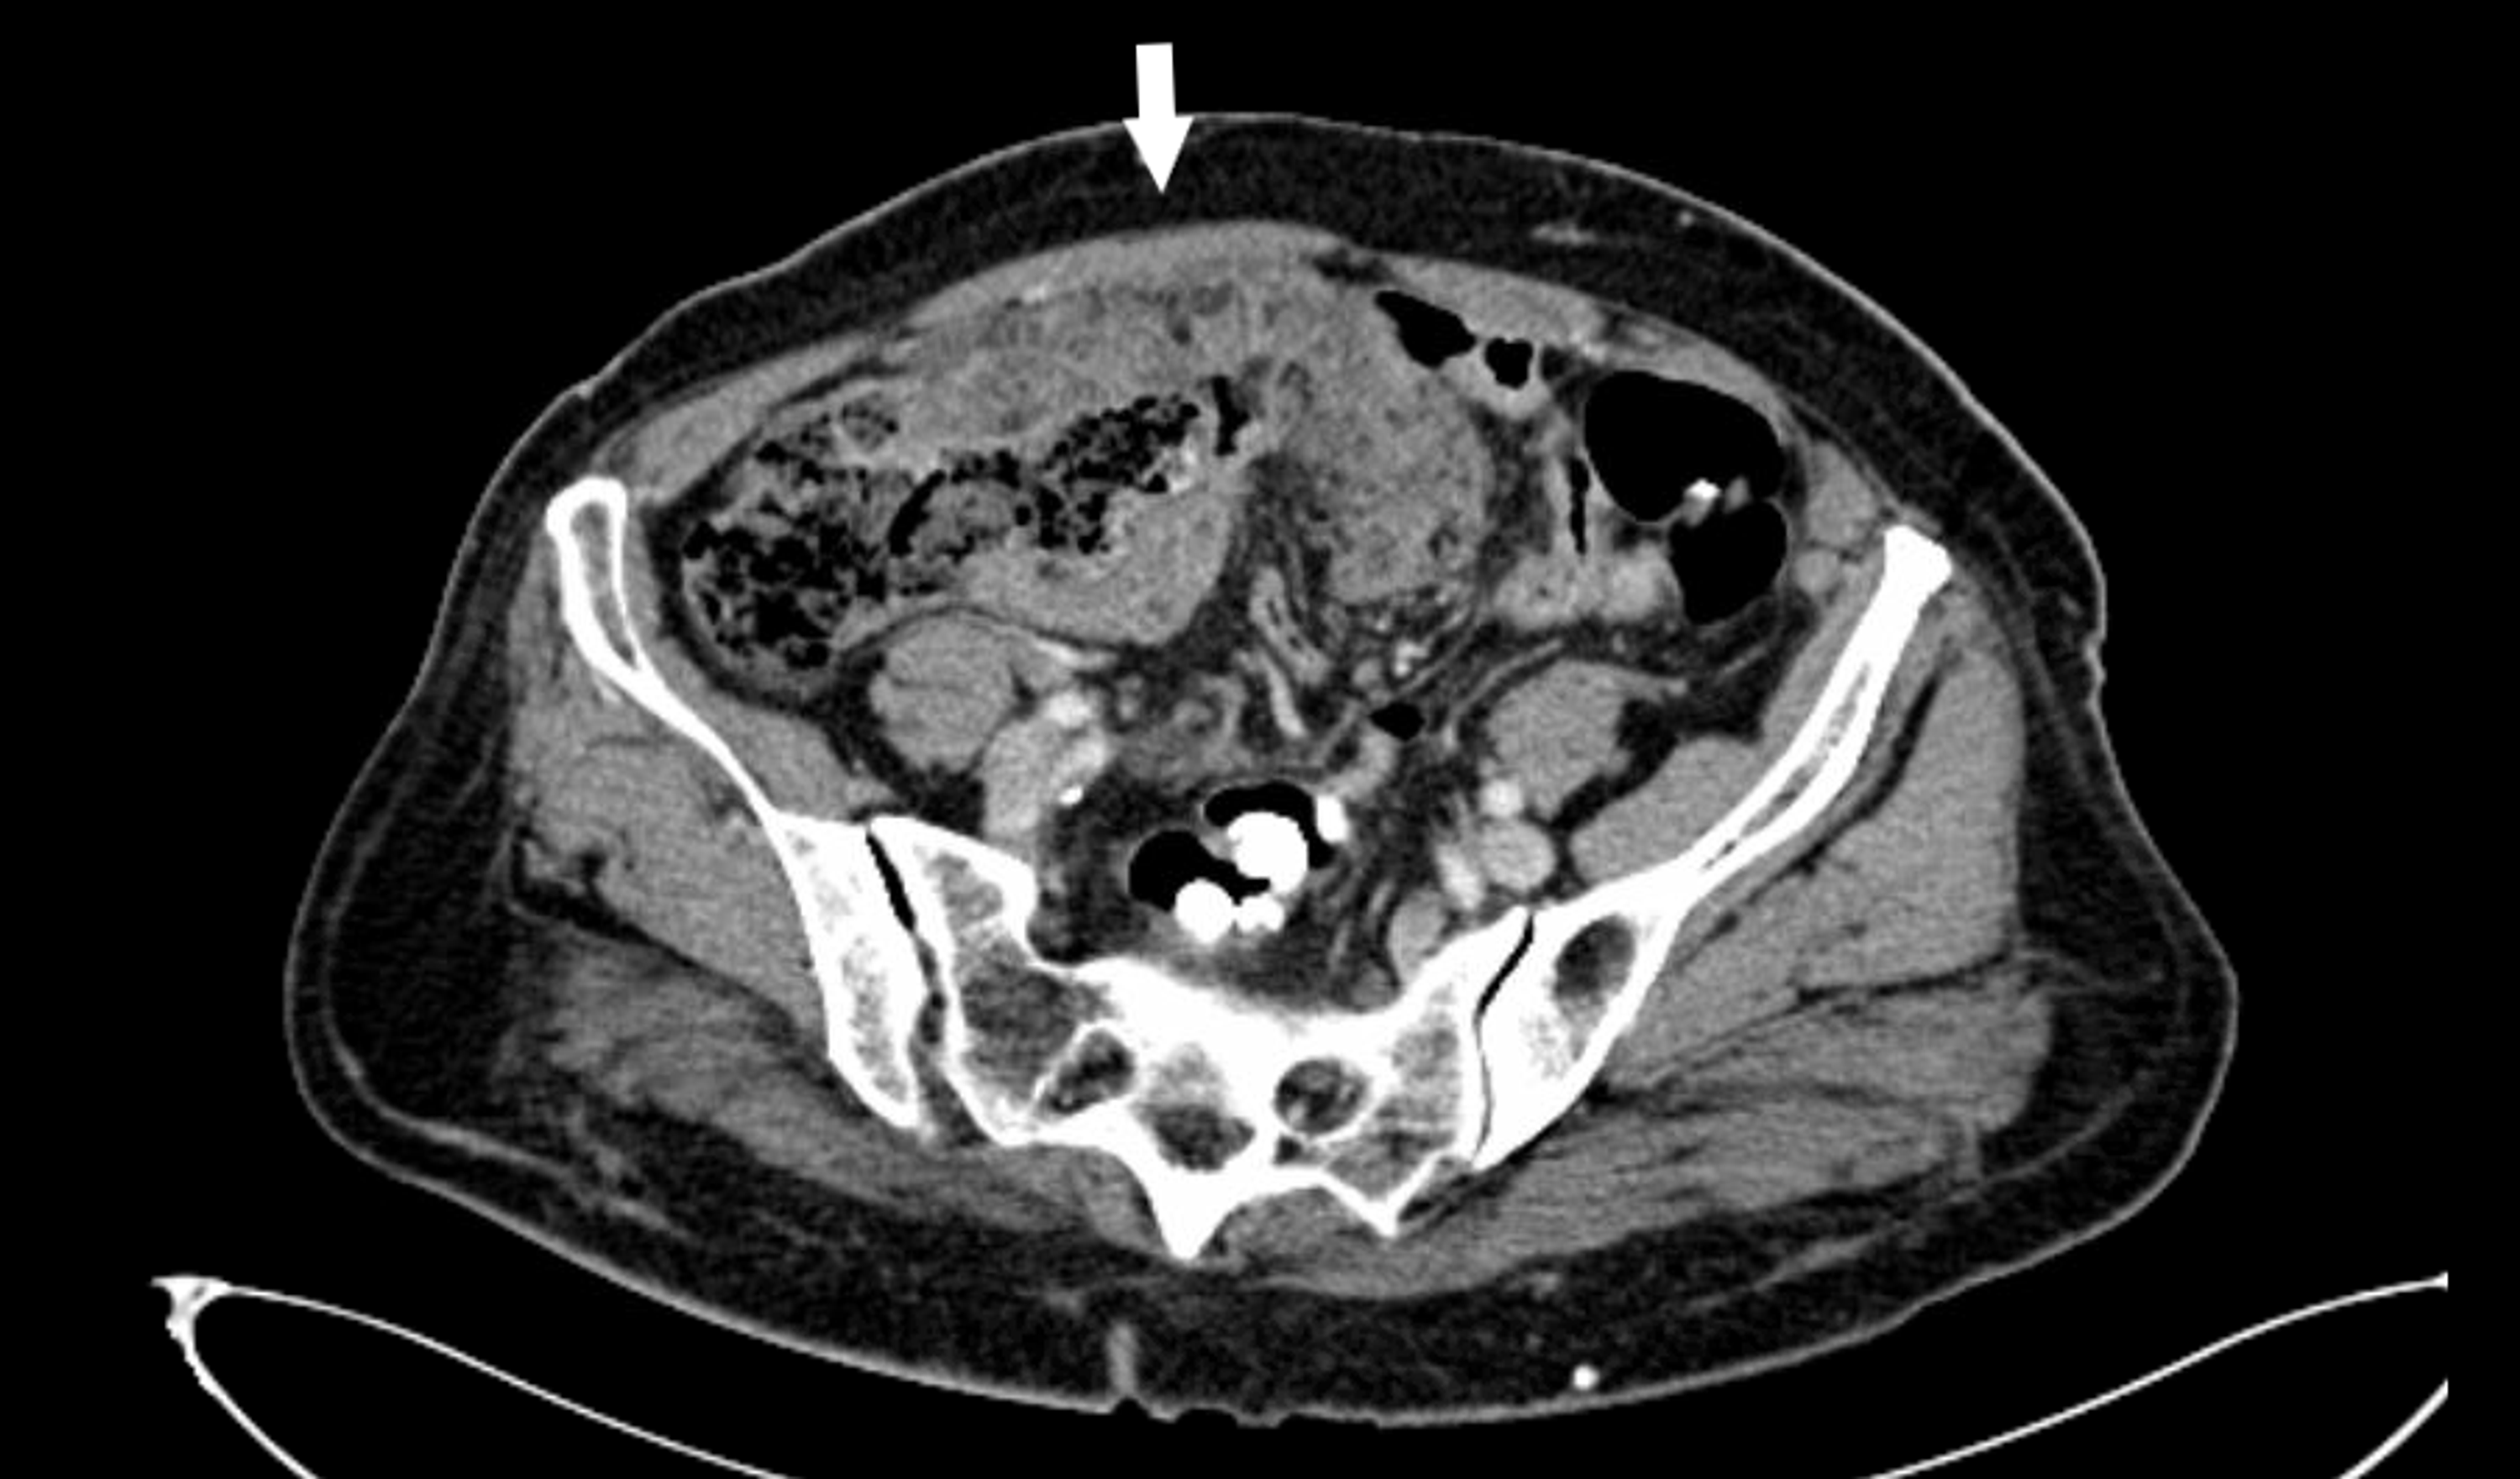

From www.researchgate.net

Abdominal computed tomography showing peritoneal carcinomatosis Abdominal Carcinomatosis Definition Cancer that has spread to the lining surfaces of the peritoneal (abdominal) cavity from ovarian cancer, primary colorectal cancer, appendiceal. Peritoneal carcinomatosis is most often. It’s sometimes called primary peritoneal. The peritoneum is a thin membrane that covers most abdominal organs and lines the abdominal cavity. Peritoneal cancer is a rare cancer. Peritoneal carcinomatosis is a rare form of cancer. Abdominal Carcinomatosis Definition.